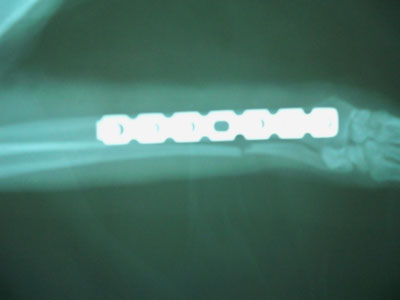

Mετά την ανάταξη του κατάγματος τοποθετήθηκε μεταλλική πλάκα 2mm στην πρόσθια επιφάνεια της κερκίδας με 3 κοχλίες στο κεντρικό και 3 κοχλίες στο περιφερικό τμήμα.Συρραφή του μυ΄ι΄κού τοιχώματος έγινε με interlocking ραφή και του δέρματος με π ραφές.